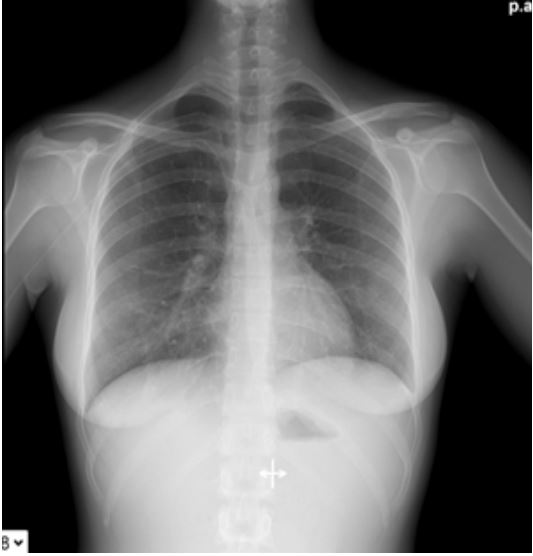

On March 8th the patient went to our Emergency Department because of worsening of symptoms. She presented with dry cough, shore throat, low grade fever (temperature 37.8°C) and shortness of breath. Blood tests showed leukocytosis (WBC 12900/µl – of which 20% were neutrophils and 65% lymphocytes) with atypical lymphocytes and liver function abnormalities (aspartate aminotransferase level 249 UI/L, alanine aminotransferase level 288 UI/L, lactate dehydrogenases 360 mg/dl). C-reactive protein was unremarkable (1 mg/l; reference interval 0-0.5 mg/l). A blood gas analyses showed respiratory failure (pO2 62, pCo2 34). Sars-Cov2 smear was repeated and confirmed negative. A CT-scan was also performed and showed bilateral small random nodules without a particular topographic distribution and associated with air space consolidation in posterior basal lung segments (Figure 2).

Figure 2: Bilateral small random nodules associated with air space consolidation in posterior basal lung seen at CT scan